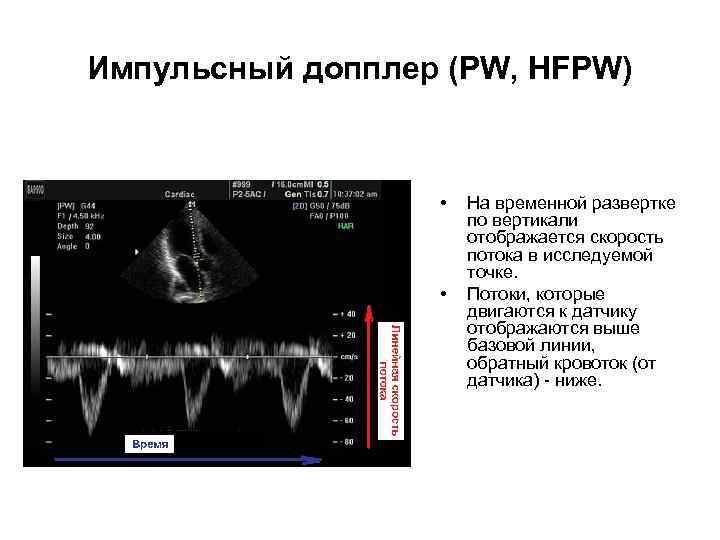

Импульсный допплер (PW, HFPW) • • На временной развертке по вертикали отображается скорость потока в исследуемой точке. Потоки, которые двигаются к датчику отображаются выше базовой линии, обратный кровоток (от датчика) - ниже.

Импульсный допплер (PW, HFPW) • • На временной развертке по вертикали отображается скорость потока в исследуемой точке. Потоки, которые двигаются к датчику отображаются выше базовой линии, обратный кровоток (от датчика) - ниже.

Импульсный допплер (PW, HFPW) • Максимальная скорость потока зависит от глубины сканирования, частоты импульсов и имеет ограничение (около 2, 5 м/с при диагностике сердца). • Высокочастотный импульсный допплер (HFPW - high frequency pulsed wave) позволяет регистрировать скорости потока большей скорости, однако тоже имеет ограничение, связанное с искажением допплеровского спектра. • В эхокардиографии, помимо формы и характера кровотока, с помощью импульсного допплера можно зафиксировать щелчки открытия и закрытия створок клапанов, дополнительные сигналы от хорд створок и стенок сердца.

Импульсный допплер (PW, HFPW) • Максимальная скорость потока зависит от глубины сканирования, частоты импульсов и имеет ограничение (около 2, 5 м/с при диагностике сердца). • Высокочастотный импульсный допплер (HFPW - high frequency pulsed wave) позволяет регистрировать скорости потока большей скорости, однако тоже имеет ограничение, связанное с искажением допплеровского спектра. • В эхокардиографии, помимо формы и характера кровотока, с помощью импульсного допплера можно зафиксировать щелчки открытия и закрытия створок клапанов, дополнительные сигналы от хорд створок и стенок сердца.